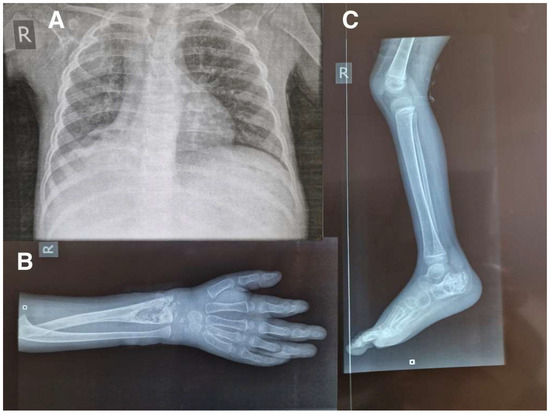

Successful Management, in a Low-Resource Setting, of Disseminated Tuberculosis in a 3-Year Old Boy: A Case Report

2. Case Report